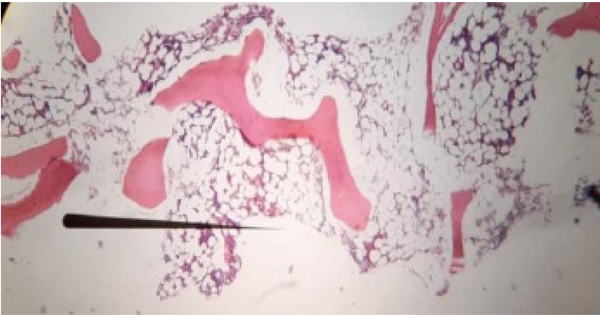

Por su historia de uso de mmi y sospecha de aa, se le realizó una biopsia y aspirado de médula ósea con documentación en la citometría de flujo y mielograma de disminución de todas las líneas celulares dado por neutrófilos: 2.3 %, linfocitos B: 2.2 % politípicos y linfocitos T: 2.5 %, sugestivos de aa (figuras 1 y 2). Al quinto día de hospitalización, se recibió el resultado de la biopsia de médula ósea con hallazgos morfológicos indicativos de aa.

Figura 1 Coloración hematoxilina-eosina de la médula ósea en 4X. Espacios trabeculares con aproximadamente un 10 % de celularidad